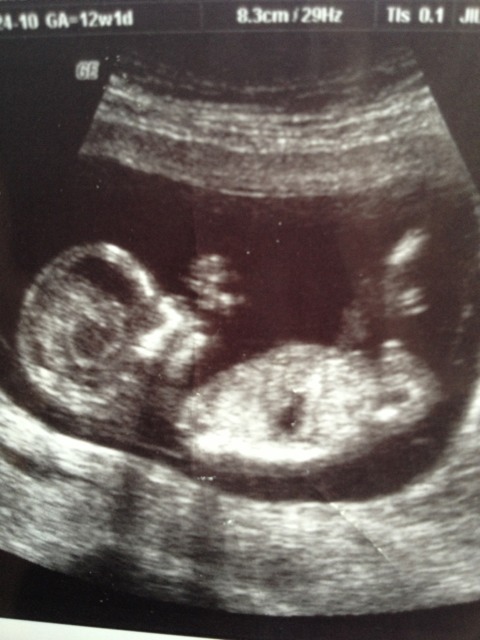

Is this a very obvious boy nub or not a nub?

The first picture--nub? And I was 12.1 weeks

I have to say that the top pic does look boyish to me, hope I'm wrong xx

Looks like a boy nub in first picture.

That's a boy nub in pic one

First picture looks like an obvious boy nub. I don't see a nub in the other photos ...